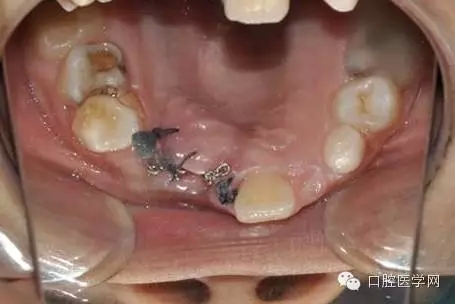

光固化型正畸粘結(jié)劑粘結(jié)鏈?zhǔn)綘恳b置

29.webp.jpg

鏈狀正畸牽引裝置粘固后的口內(nèi)情況